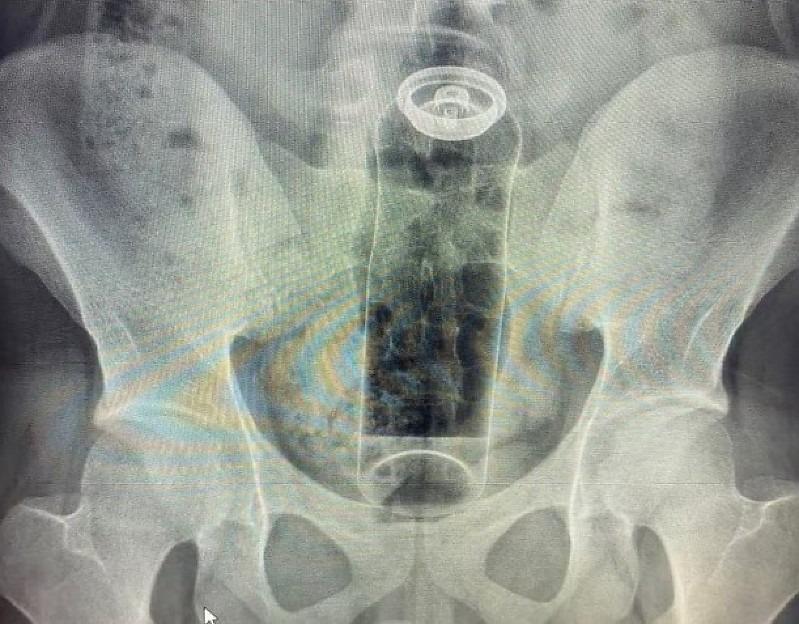

Jovem de 19 anos é internado após desodorante ficar preso no ânus

Médico disse que casos como esse têm se tornado frequentes